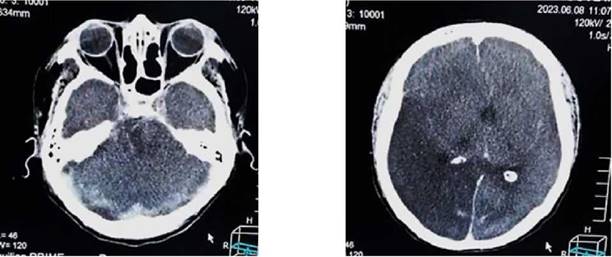

La evolución posterior se caracterizó por permanecer estable hemodinamicamente, con mejor control de la presión arterial, sin deterioro neurológico, bajo terapia de reemplazo renal; sin embargo al sexto día, en forma súbita presenta mayor deterioro neurológico con un Glasgow de 9-10/15 y mala mecánica ventilatoria, rápidamente se intuba a la paciente para protección de vía aérea, asociado a analgo-sedación; se optimizan las medidas de protección cerebral y se realiza un control tomográfico (Figura 3a, b).

Figura 3a, b: tomografía cráneo simple, hemorragia subaracnoidea difusa, sangrado ventricular desviación leve de la línea media.

Aun a pesar del tratamiento instaurado de forma multidisciplinaria, permaneció con tendencia a la hipertensión arterial de difícil manejo, bajo analgo-sedación, en asistencia respiratoria mecánica, nuevamente con vasodilatadores endovenosos y medidas de protección cerebral (en primera línea); a las 2 semanas de hospitalización con más deterioro neurológico disminución de los reflejos del tallo cerebral, con tendencia a la bradicardia e hipertensión arterial extrema (probable síndrome de Cushing), se realiza una nueva TAC de cráneo que muestra importante edema cerebral con borramiento de las cisternas peri mesencefálica, compatible con un deterioro rostro caudal (Figura 4a, b)

Figura 4a, b: tomografía de cráneo simple se evidencia edema cerebral generalizado, borramiento de cisterna perimesencefalicas, área de isquemia en hemisferio derecho y desviación marcada de línea media (flechas rojas).